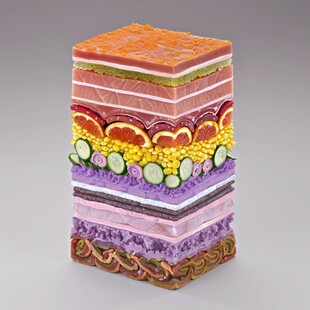

皮肤结构图 非商作品

皮肤结构图 非商作品 -

毛囊 共享分: 100

毛囊 共享分: 100 -